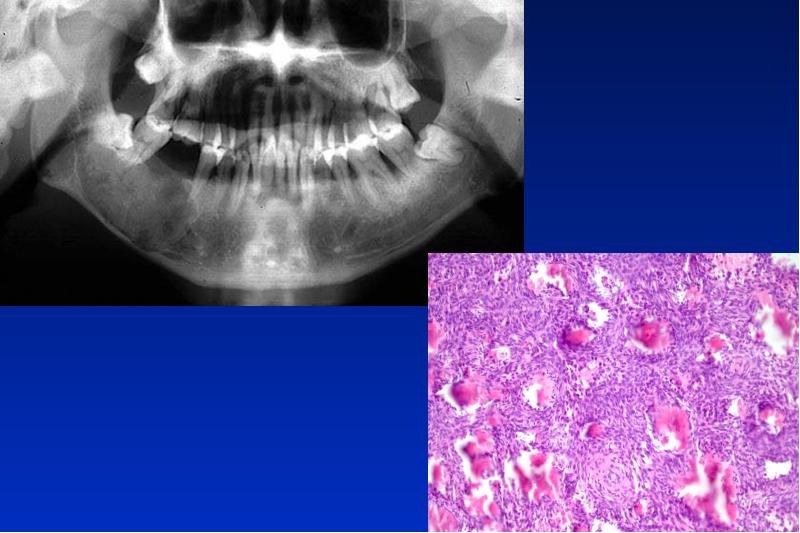

- 85. Cherubismus autosomal dominant vererbtes Krankheitsbild mit symmetrischer Kieferauftreibung im Kindesalter und